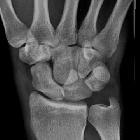

lunate dislocation

Lunate dislocations are an uncommon traumatic wrist injury that require prompt management and surgical repair. The lunate is displaced and rotated volarly. The rest of the carpal bones are in a normal anatomic position in relation to the radius.

- AP radiograph

- dislocation is often overlooked

- disruption of the normally smooth line made by tracing the proximal articular surfaces of the hamate and capitate

- increased radiolunate space

- lunate overlaps the capitate and has a 'triangular' or 'piece of pie' appearance